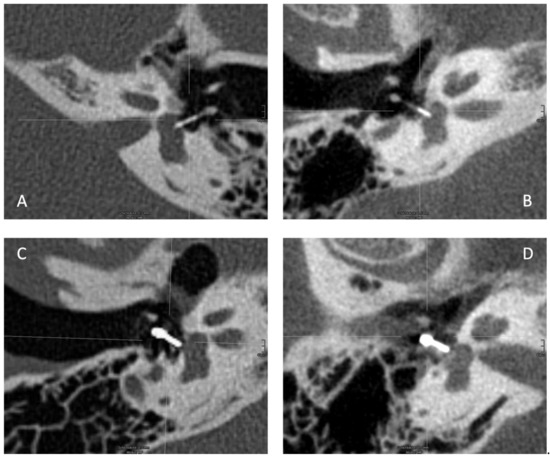

:1. Introduction

2.2. Data Collection and Measurements

2.3. Prostheses Types

2.4. Computed Tomography and Cone Beam Computed Tomography